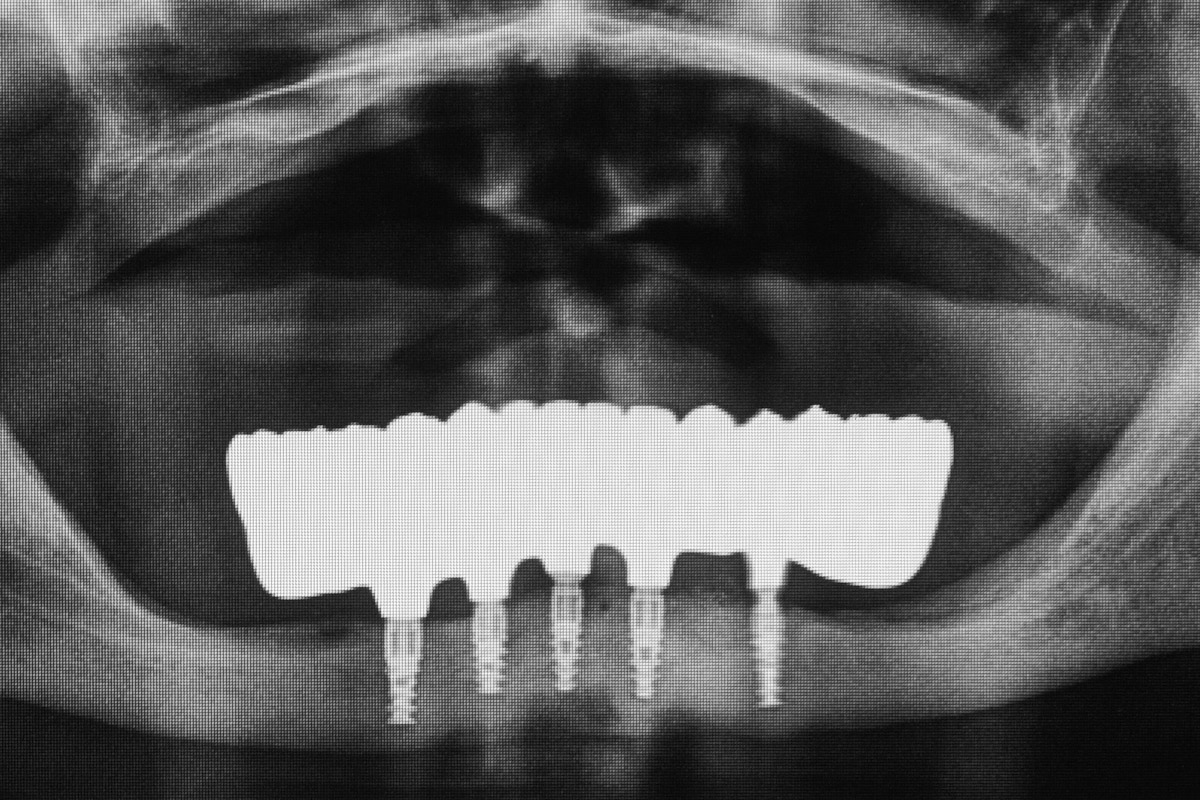

ALL-ON-4

- ALL-ON-4 to sprawdzona i przewidywalna metoda odbudowy uzębienia na implantach dla bezzębnych pacjentów. To opatentowany system rehabilitacji opartej na 4 wszczepionych implantach, gdzie 2 środkowe są wprowadzone równolegle, 2 skrajne – skośnie, pod kątem 45 stopni.

- ALL-ON-4 to sprawdzona i przewidywalna metoda odbudowy uzębienia na implantach dla bezzębnych pacjentów. To opatentowany system rehabilitacji implantoprotetycznej oparty na 4 wszczepionych implantach, gdzie 2 środkowe są wprowadzone równolegle, 2 skrajne – skośnie, pod kątem 45 stopni.

Jest to opatentowana metoda rekonstrukcji implanto-protetycznej kompletnego uzębienia stosowana przy bezzębiu zarówno dla dolnego, jak i górnego łuku zębowego. Bazuje na charakterystycznie wszczepionych 4 implantach zębowych, stąd nazwa Wszystko na 4. Dwa środkowe wprowadzane są w kość prostopadle do jej brzegu i równolegle do siebie, dwa boczne wszczepiane są pod kątem 45 stopni. Rozwiązanie protetyczne to most przykręcany na stałe do implantów, który może być zakładany natychmiast po zabiegu implantacji lub w czasie odroczonym. Gwarancją natychmiastowego przywrócenia funkcji żucia jest odpowiednia siła osadzania implantów mierzona dynamometrycznie w trakcie ich wszczepiania oraz należyta staranność wykonania i osadzenia prac protetycznych.